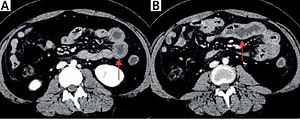

Mesenteric vasculitis with inferior vena cava thrombosis associated with systemic lupus erythematosus

Arch Med Sci 2023;19(2):544-545